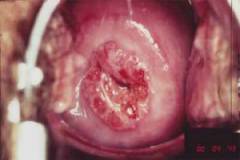

Плоскоклеточный рак шейки матки

Основным фактором, способствующим возникновению данного заболевания, является вирус папилломы человека, обнаруживаемый почти у 75% женщин, больных раком шейки матки.

Слизистая оболочка влагалища и влагалищная часть шейки матки покрыты многослойным плоским неороговевающим эпителием. Плоскоклеточный рак чаще развивается в области перехода многослойного плоского эпителия в цилиндрический (выстилающий внутренний зев и полость матки).

Симптомы злокачественного новообразования на начальных стадиях неспецифичны и могут проявляться при других заболеваниях мочеполовой системы.

Признаками рака шейки матки могут быть:

- кровотечения из влагалища вне менструации;

- кровотечения после полового акта;

- боль во время полового акта;

- постоянные ноющие боли внизу живота;

- нарушение мочеиспускания и дефекации.